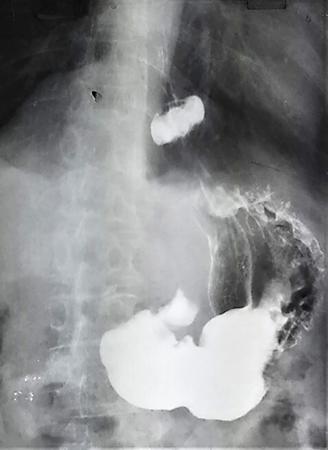

Single contrast barium study (Fig. 7.4.5.1), CECT (Figs. 7.4.5.2 and 7.4.5.3).

Fig 7.4.5.1 Barium study of the patient.

Fig 7.4.5.2 CECT of the patient.

Fig 7.4.5.3 CECT of the patient.

Observations

Barium study shows large filling defect in the antrum forming acute angles with the wall. Undulating contour is seen along greater curvature with ulceration of overlying mucosal irregularity.

CECT shows a large lobulated mass involving lesser curvature and antrum with marked wall thickening along distal greater curvature.

Diagnosis

Carcinoma stomach.